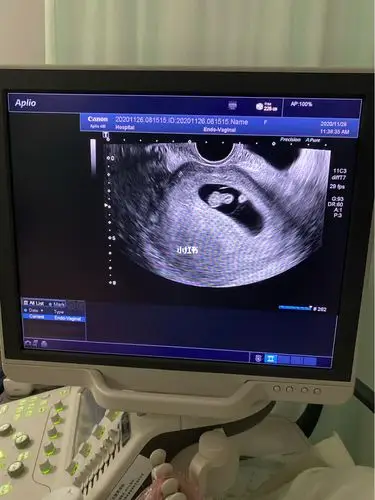

8周的第一张照片